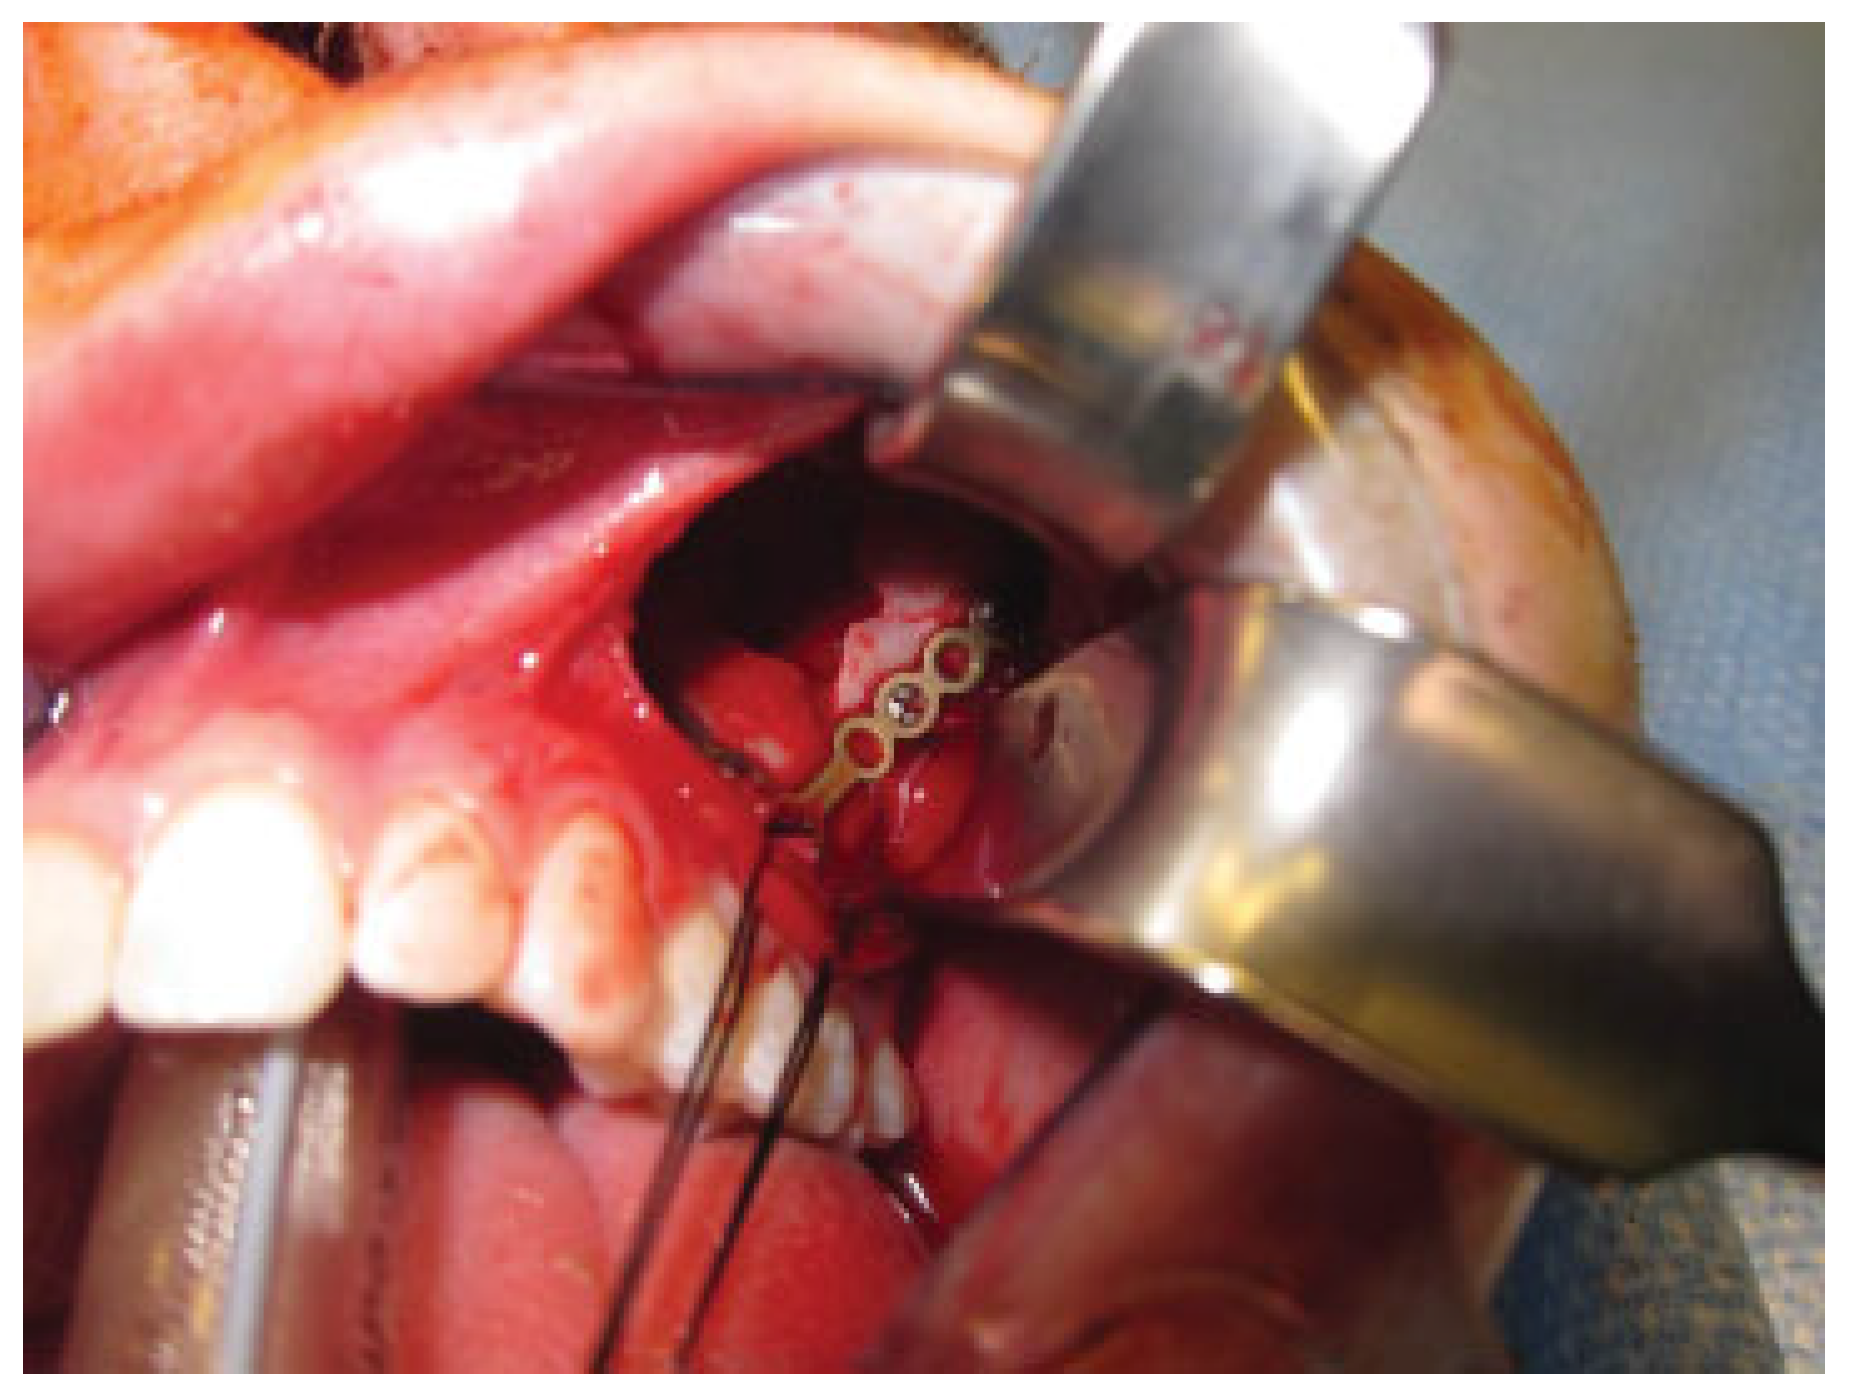

The patient was taken to the operating room approximately 16 hours following injury for open reduction and internal fixation. He was intubated orally and a corneal shield was placed for protection of the left globe. The left zygomatico-maxillary buttress was subsequently exposed using a standard gingivobuccal sulcus incision (Figure 3). The body of the zygoma was mobilized using a curve Kelly clamp and reduction was achieved at the zygomaticomaxillary buttress. The infraorbital rim was directly visualized and noted to be in anatomic alignment. Palpation of the frontozygomatic suture did not reveal obvious step-off. As such, fixation was applied at the zygomaticomaxillary buttress using a 0.7-mm-thick L-shaped 1.5 medium plate (DePuy Synthes, West Chester, PA) (Figure 4).

Figure 3. Intraoperative view of displaced zygomatic body. The zygo-matic body was exposed via a gingivobuccal sulcus incision, with significant posterior displacement noted.